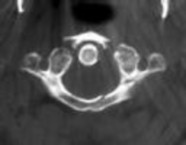

CLINICAL SITUATION

Figure 1 shows a CT from the cervical spine of an 85-year-old woman who fell from a standing height 1 week earlier. She is independent and ambulatory and resides in an assisted living facility. She reports persistent neck pain but denies arm pain or weakness. She is neurologically intact.

Fractures in this region of C2 have a high risk of

Discussion: C

Increased displacement and angulation of odontoid fractures have an increased risk of nonunion. Surgical stabilization has reduced the risks of mortality without increasing the risk of complications compared with nonsurgical treatment options. When treating odontoid fractures, halo vest

immobilization has been shown to increase the risk of dysphagia in the elderly.

The preferred mode of treatment for this patient’s fracture is

4. posterior C1-2 arthrodesis. Discussion: D

Increased displacement and angulation of odontoid fractures have an increased risk of nonunion. Surgical stabilization has reduced the risks of mortality without increasing the risk of complications compared with nonsurgical treatment options. When treating odontoid fractures, halo vest immobilization has been shown to increase the risk of dysphagia in the elderly.

4. Dysphonia Discussion: B

Increased displacement and angulation of odontoid fractures have an increased risk of nonunion. Surgical stabilization has reduced the risks of mortality without increasing the risk of complications compared with nonsurgical treatment